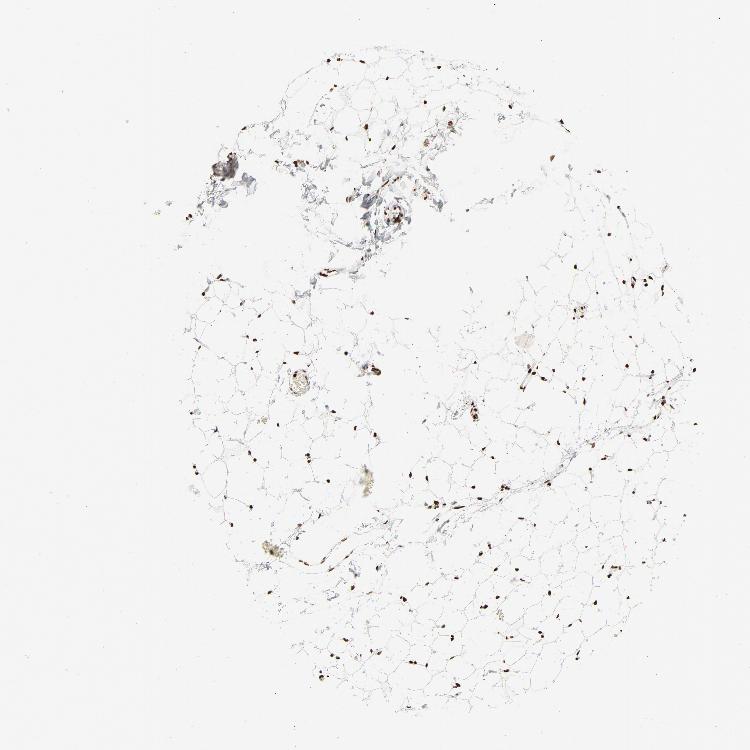

ADIPOSE TISSUE - Antibody stainingi

Antibody staining in the annotated cell types in the current human tissue is reported as not detected, low, medium, or high, based on conventional immunohistochemistry profiling in selected tissues. This score is based on the combination of the staining intensity and fraction of stained cells.

Each image is clickable and will lead to virtual microscopy that enables deeper exploration of all samples and also displays staining intensity scores, fraction scores and subcellular localization as well as patient and tissue information for each sample.

Antibody HPA003506Antibody HPA053314Antibody CAB037206

Adipocytes MediumNot detectedMedium